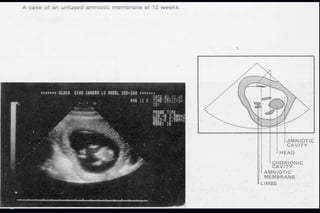

Ultrasonic Landmark Occurence

(weeks of gestation)

 Gestational sac 5 – 6 weeks

 Fetal embryonic pale 6 – 7 weeks

 Detection of fetal life 7 – 8 weeks

 Placenta 8 – 10 weeks

 Loss of gestational sac 11 – 13 weeks

 Fetal head 11 – 14 weeks

(Biparietal diameter)